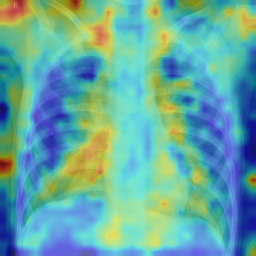

To illustrate failure cases of an anomaly detection model for bacterial pneumonia, we illustrated the heatmaps in Fig. 7. In the first example, the model misclassifies normal anatomical structures such as the cardiac border and diaphragm as abnormal regions, resulting in a false positive. In the second example, it fails to detect subtle and diffuse pulmonary opacities, leading to a false negative. These errors highlight the model’s sensitivity to normal intensity variations and its limited ability to recognize low-contrast infections.